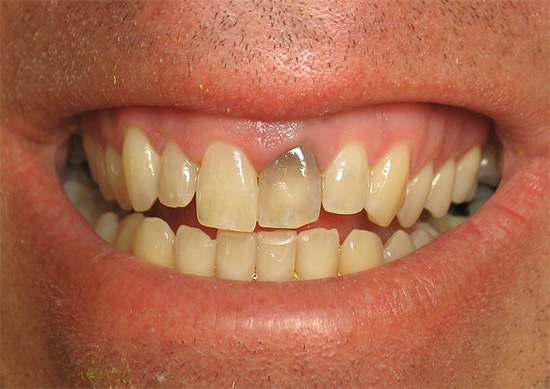

Domanda al dentista: "Perché il mio dente si oscura dopo aver rimosso un nervo?"

Dopo un trattamento di qualità dei canali, il dente di solito non si scurisce nel corso degli anni, ma diventa solo più scuro, cioè perde la sua lucentezza naturale, che non è una deviazione dalla norma.Se il dente diventa nero o giallo dopo un po 'di tempo dopo la rimozione del nervo, allora dovresti cercare la causa o nella preparazione della cavità del dente per il riempimento (in un'asportazione di scarsa qualità dei tessuti cariati) o in una scarsa elaborazione strumentale dei canali lasciando residui di nervi e infezione batterica in essi.

Inoltre, spesso un grave cambiamento nel colore della corona dentale è associato al materiale utilizzato per riempire i canali. Quindi, ad esempio, alcuni dentisti continuano a riempire per errore i canali dei denti anteriori dopo aver rimosso il nervo con Endometasone, per cui dopo alcuni anni i denti possono diventare molto gialli, il che è persino indicato nelle istruzioni per il materiale.